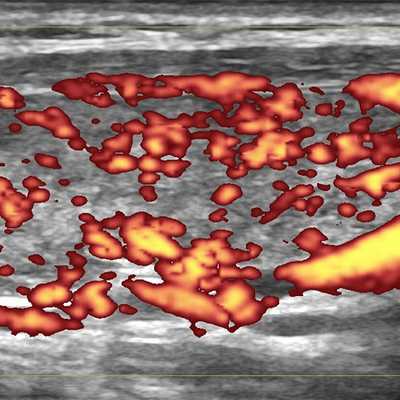

Кровоток в ЩЖ определяется в режиме ЦДК или ЭДК. Многие врачи применяют ЦДК, а не ЭДК, несмотря на меньшее количество искажений при ЭДК. Наша Клиника предлагает всем коллегам выполнять оценку интенсивности кровотока в ЩЖ с помощью ЭДК, а скорость крови в режиме ЦДК, так как ЦДК позволяет цветом различать артерии от вен.

Рисунок 2. Два варианта ультразвукового допплеровского режима ― ЦДК (цветовое допплеровское картирование) и ЭДК (энергетическое допплеровское картирование). Программа УЗ-аппарата показывает сосуды цветом. Красным и синим при ЦДК и алым ― при ЭДК. При ЦДК видны сосуды (артерии и вены), несущие кровь в разных направлениях). При ЭДК не видно направления течения крови, но меньше погрешностей.